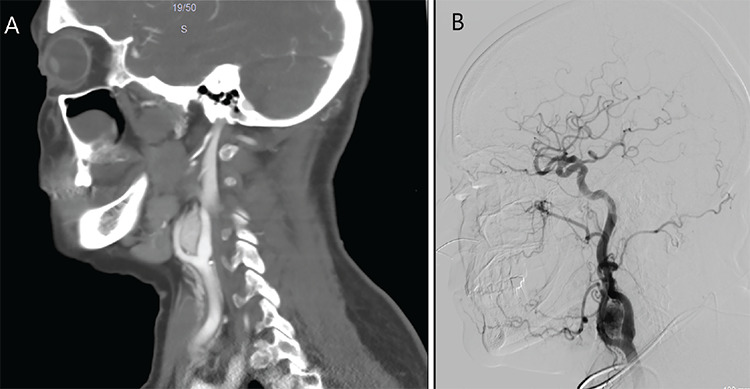

Objective: To investigate head and neck paraganglioma cases treated at a tertiary center from 2007 to 2023. The research includes a thorough examination of published studies that have focused on long-term outcomes. The additional goal is to contribute to the existing knowledge on head and neck paraganglioma, with a particular emphasis on refining diagnostic algorithms, treatment selection, and follow-up procedures.

Methods: A total of 44 patients were retrospectively analyzed, and 39 were included. Demographic information, symptoms, radiological examination results, types, stages, and postoperative complications were recorded. A review was conducted to select articles that reported single-center experiences with large cohorts, long follow-ups, and different treatment modalities since 2010.

Results: The mean age of the patients was 54 years, and the female/male ratio was 3.55:1. Among the 39 cases examined, 18 and 19 were identified as cervical paraganglioma and 19 as temporal bone paraganglioma. All patients initially underwent surgical resection. The mean follow-up duration was 5.42 years. Four residual cases and two recurrences were identified postoperatively, and a Gamma Knife was used as additional treatment. Subsequently, 17 articles were selected and summarized, and then a flowchart was prepared showing the possible options for diagnosis, treatment, and follow-up.

Conclusions: Preoperative staging is essential for surgical planning and predicting potential intraoperative complications. Based on our findings and review of the articles, we have prepared a flowchart that includes all possibilities depending on the tumor stage to help in the diagnosis, treatment, and follow-up of head and neck paragangliomas.